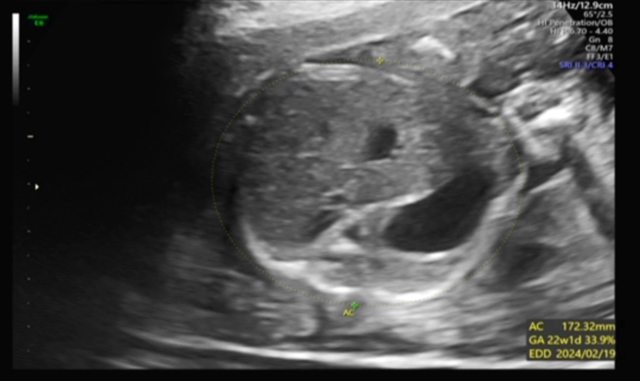

昨天去產檢,醫生覺得寶寶的胃偏大之後要注意觀察 我搜尋了一下好像只有看到胃太小的文,請問大家有沒有遇過類似情況? 我後來看了一下22週的高層次照片,那時候寶寶也是胃大大的,但那時只說是寶寶可能剛 吃飽 https://i.imgur.com/amlKp09.jpg

smilemibo : 我也在二十週左右超音波照出小孩胃偏大,但觀察了兩 11/24 15:18

smilemibo : 三週之後又恢復正常了,現在出生一切正常,醫生也說 11/24 15:18

smilemibo : 膀胱跟胃有可能因為剛吃飽或者還沒排泄剛好被照到所 11/24 15:18

smilemibo : 以會比較大 11/24 15:18